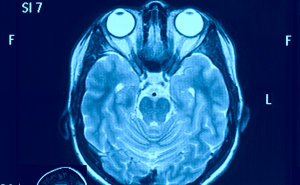

Mehr erfahren zu: "Visueller Kortex: Kurze Nervenfasern sichtbar gemacht" Visueller Kortex: Kurze Nervenfasern sichtbar gemacht Wissenschaftlern vom Max-Planck-Institut für Kognitions- und Neurowissenschaften in Leipzig ist es gelungen, die kurzen neuronalen Fasern mithilfe der Magnetresonanztomographie (MRT) im lebenden menschlichen Gehirn sichtbar zu machen.